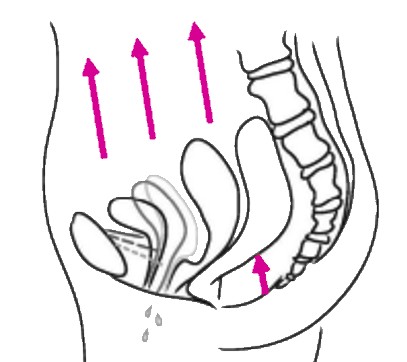

Then, you reprogram the pelvic floor to coactivate with the diaphragm: When you inhale, the pelvic floor extends and relaxes, when you exhale, it lifts and the muscles contract.

It is like training any muscle: contraction and relaxation. So you tone & strengthen the pelvic floor, but also teach it to relax. This means less incontinence, reducing prolapse symptoms, and also less abdominal pain, eg. during period.

The pelvic floor

Responsible for the flexible support of the uterus, the bladder and also the rectum. You will learn how to activate and to relax it, and also physically to lift it. As a consequence, incontinence and prolapses can be reduced, sexual function can improve, period pain can decrease.